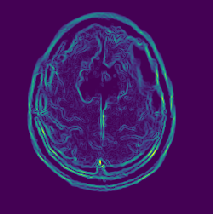

Visual inspection: An overview of the preprocessing for normal MRI can be seen in Fig. 10. The preprocessing for benign MRI can be seen in the Fig. 11 and malignant MRI can be seen in the Fig. 12.

To have a good demonstration of the preprocessing, three MRI images are considered, one is normal which is shown in Fig. 10(a), that is, without any neoplasm, the second one with benign neoplasm which is shown in Fig. 11(a) and the third one with malignant neoplasm which is shown in Fig. 12(a).The contour is plotted for three different MRI images, each for normal (see Fig.10(b)) , benign (see Fig.11(b)), and malignant (see Fig. 12(b)). Similar to contour, Sobel egdes are shown for the three MRI images: normal ()in Fig. 10(c)), benign (in Fig.11(c)), and malignant (in Fig. 12(c)). The final result after taking difference is shown for the three MRI images, normal (Fig. 10(d)), benign (Fig. 11(d)), and malignant (Fig. 12(d)).

Refer to caption

(a) Malignant GS

(b) Malignant CT

(c) Malignant SE

(d) Malignant SD

Figure 12: Proposed preprocessing applied over malignant MRI images.

Figure-12 shows a transition of the various stages of the proposed preprocessing for a malignant brain neoplasm. The contour of the malignant brain produces a centralized yellow region as seen in Fig. 12(b). But when compared with the difference contour, the less interesting regions are colored green with a brown border as previously seen with benign MRI. Further, a brown edge with yellow is is seen in the final image where the malignant neoplasm is present as seen in Fig. 12(d). The proposed preprocessing can outline the portion with the brain tumor effectively, even if the tumor is discreetly spaced. Further, many preprocessing techniques tend to over soften the image during the noise removal process to get better accuracy, but this changes the original image features. This proves to be beneficial when detecting the presence of neoplasm but during the classification of the severity, this process fails to get good results. But in the case of the proposed preprocessing, the final output MRI image is free of over softness and hence the features are preserved better.